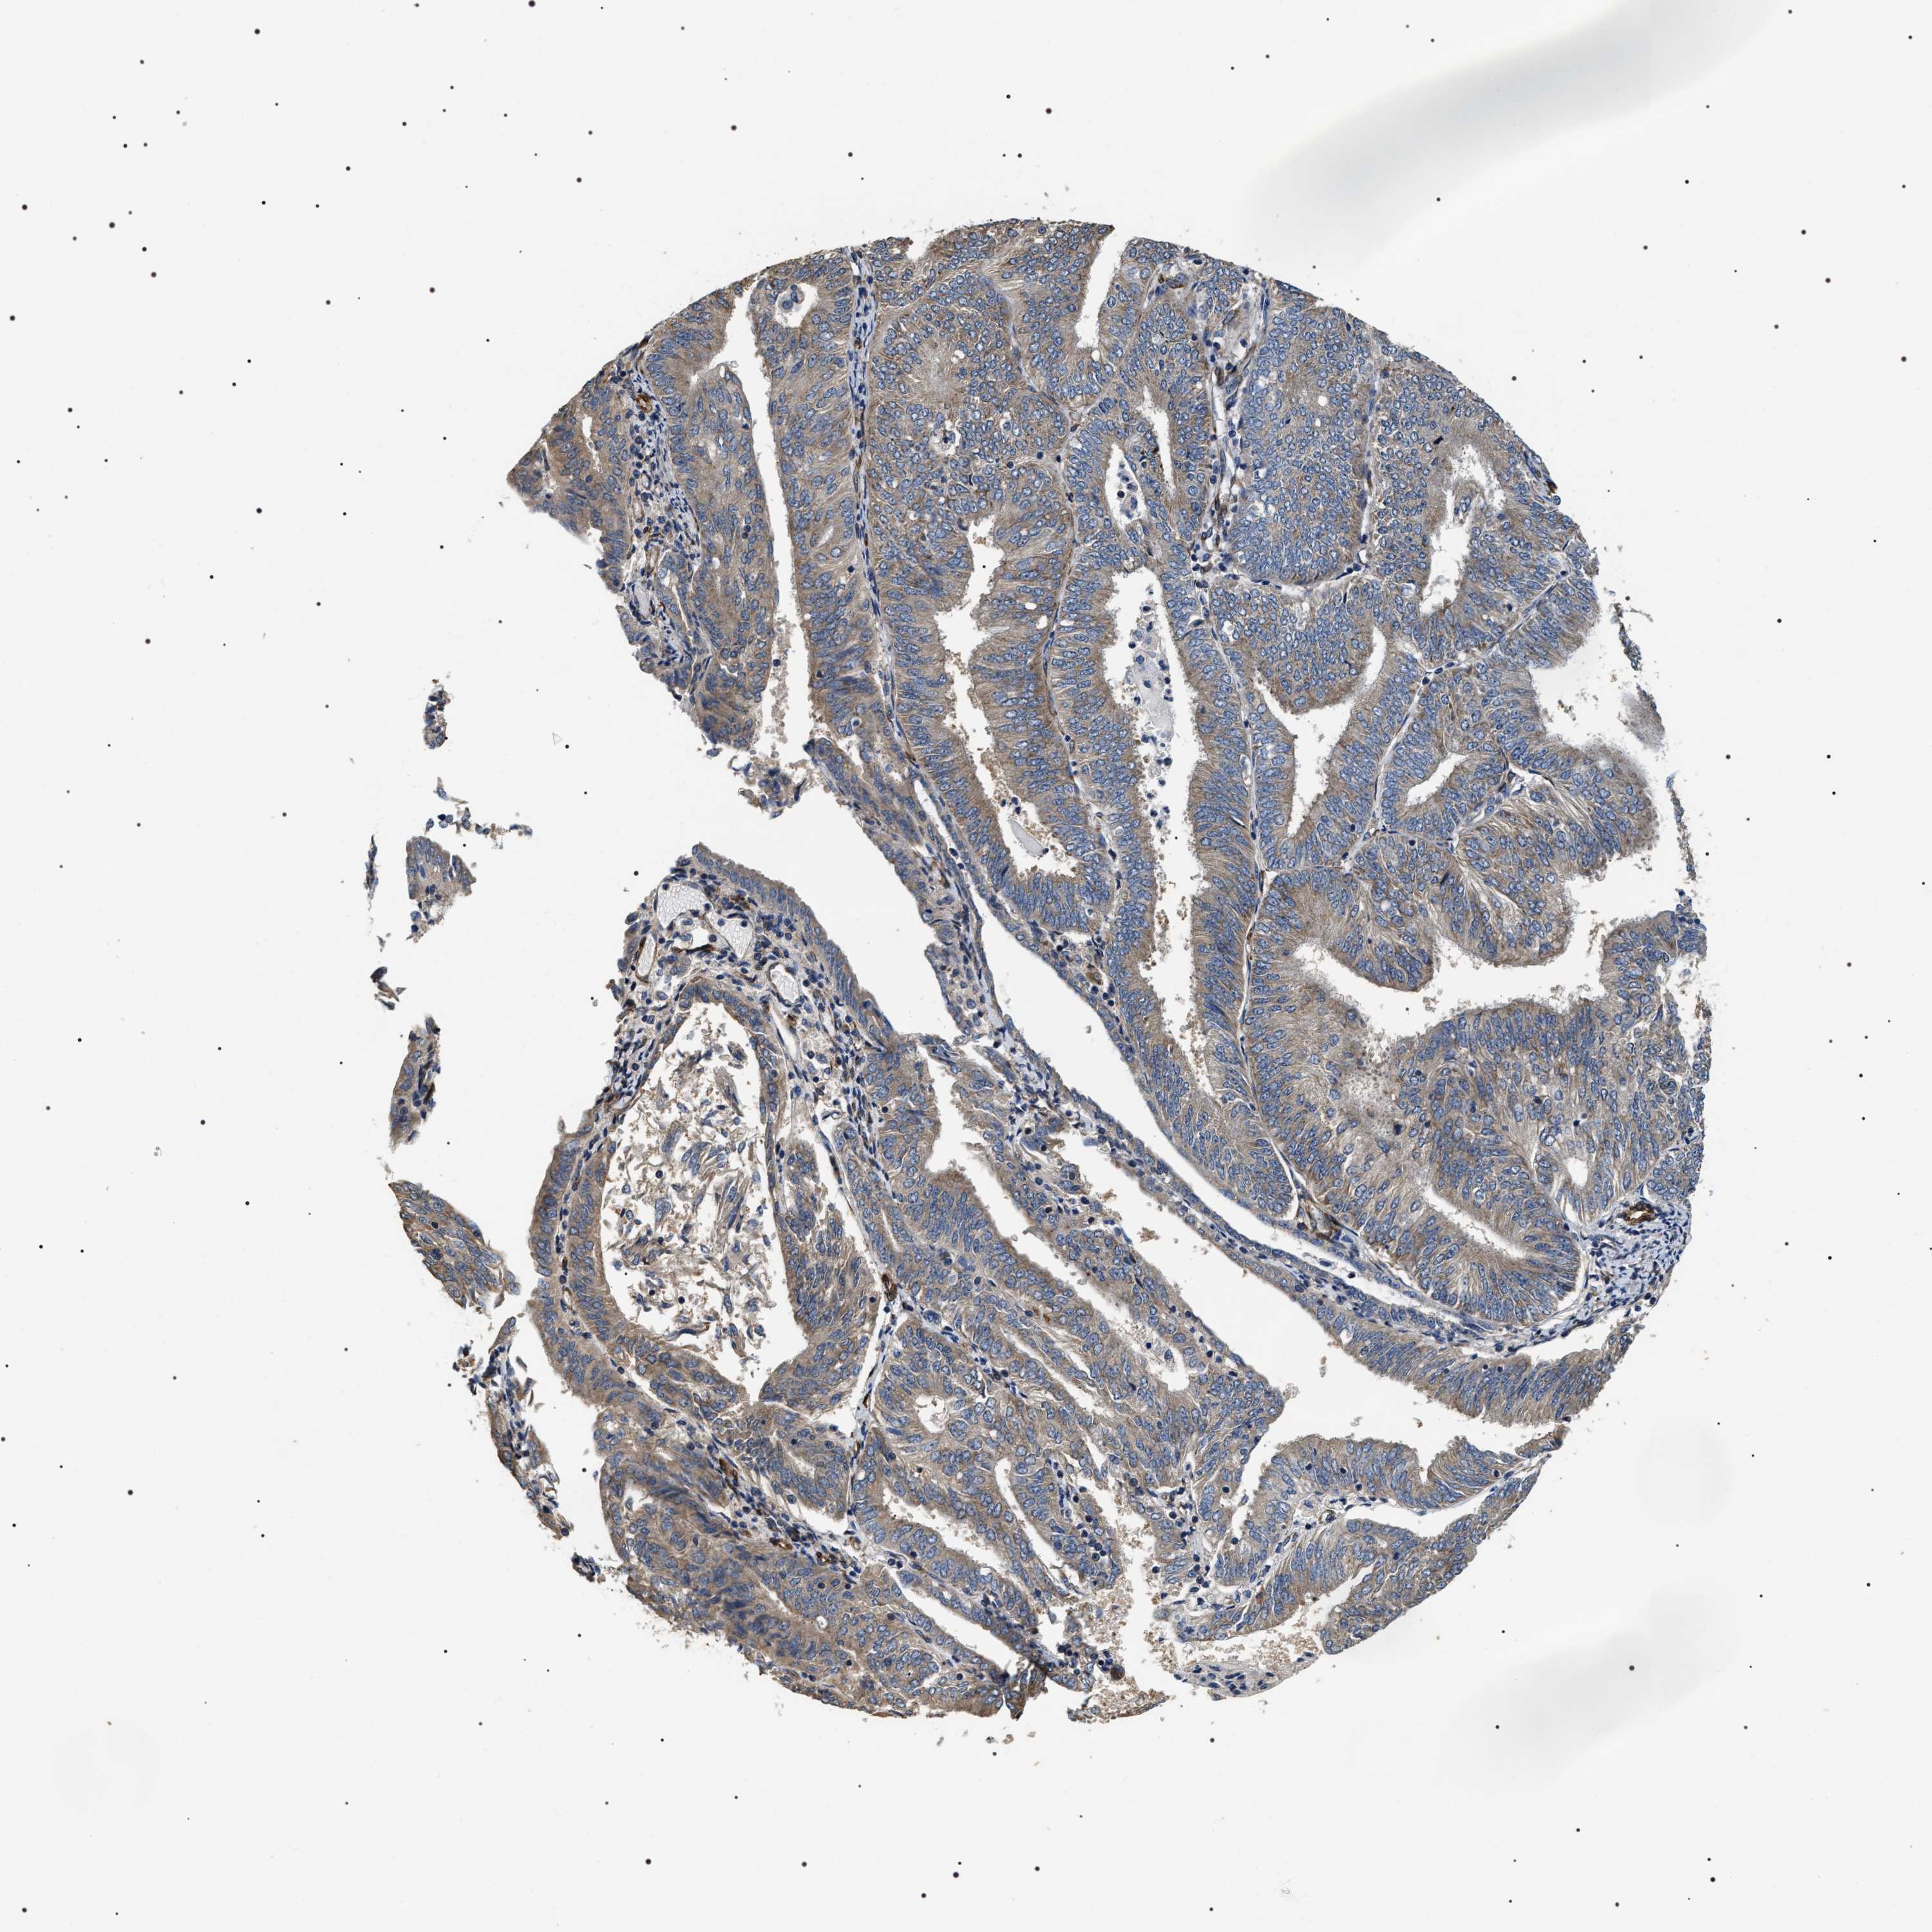

ENDOMETRIAL CANCER - Protein expressioni

A mouse-over function shows sample information and annotation data. Click on an image to view it in a full screen mode. Samples can be filtered based on level of antibody staining by selecting one or several of the following categories: high, medium, low and not detected. The assay and annotation is described here.

Note that samples used for immunohistochemistry by the Human Protein Atlas do not correspond to samples in the TCGA dataset.

Antibody stainingi

Antibody staining in the annotated cell types in the current human tissue is reported as not detected, low, medium, or high, based on conventional immunohistochemistry profiling in selected tissues. This score is based on the combination of the staining intensity and fraction of stained cells.

Each image is clickable and will lead to virtual microscopy that enables deeper exploration of all samples and also displays staining intensity scores, fraction scores and subcellular localization as well as patient and tissue information for each sample.

Antibody HPA020386

Staining

High

Medium

Low

Not detected

Intensity

Strong

Moderate

Weak

Negative

Quantity

>75%

75%-25%

<25%

None

Location

Nuclear

Cytoplasmic/membranous

Cytoplasmic/membranous,nuclear

Adenocarcinoma, NOS

Adenoma, NOS